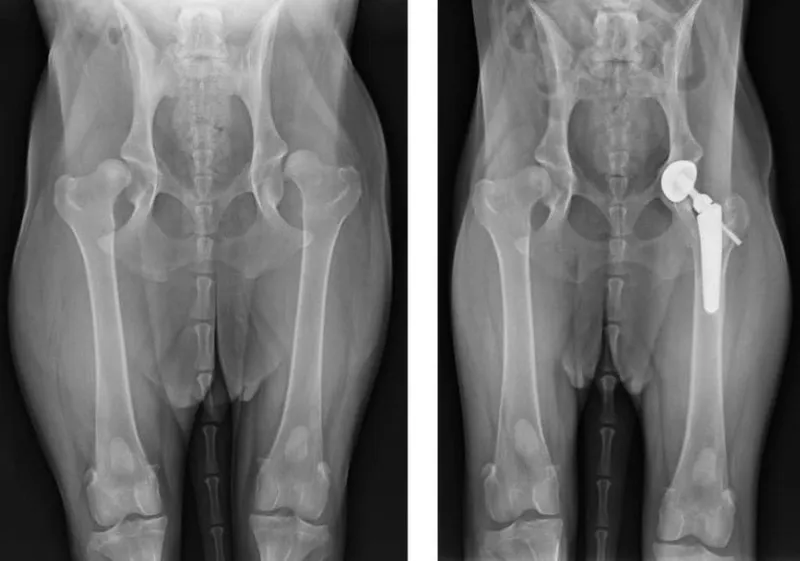

- Trật khớp háng (Hip Luxation): Thường do chấn thương mạnh, chỏm xương đùi bị văng ra khỏi ổ cối của xương chậu. Đây là tình trạng cấp cứu, gây đau đớn tột độ và cần sự can thiệp từ bác sĩ thú y ngay lập tức để tránh hoại tử chỏm xương đùi.

- Cắt chỏm xương đùi (FHO): Áp dụng cho trật khớp háng nặng hoặc thoái hóa. Cơ thể mèo sẽ tự tạo một “khớp giả” bằng mô xơ, giúp mèo đi lại mà không còn đau đớn.